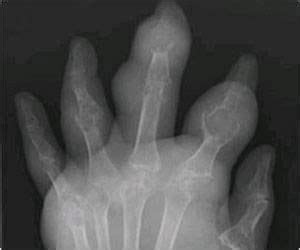

The Clinical Utility of Dual-Energy Computed Tomography in the ...

Gout: Introduction, Causes, Symptoms, Treatments

Gout

Gout GOUT